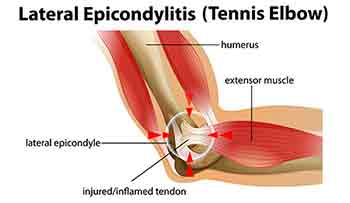

These conditions are usually described as above but are usually due to the attachment of the tendons where they meet the elbow. They will radiate pain all around one side or the other. This common condition does not involve inflammation or swelling of the elbow joint and is amenable to mobilization techniques combined with softening of the attachments. Pain can also extend along the forearm.